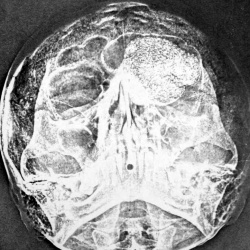

Сразу же приношу свои извинения за качество. Сохранился только один телефонный снимок одного скана, постарался сделать все возможное...не обессудьте.. Касаемо ситуации - травма...на краниограмаах 9не...